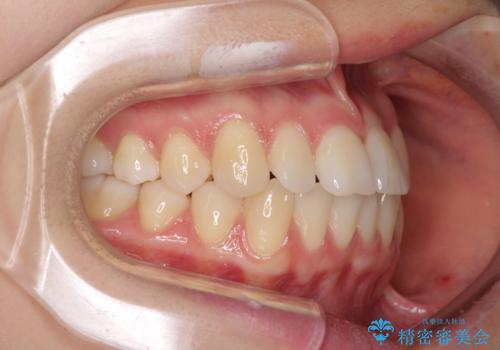

前歯のクロスバイト インビザラインによる矯正治療

- 前歯のクロスバイトを気にして来院された患者様です。

短期間での治療を希望され、ワイヤー装置とインビザラインとで悩んでいましたが、自己管理を徹底すると言うことでインビザラインによる矯正治療を行うこととしました。

しっかりとインビザラインの装着時間を守っていただいたので、1年弱で矯正治療を終えることができました。